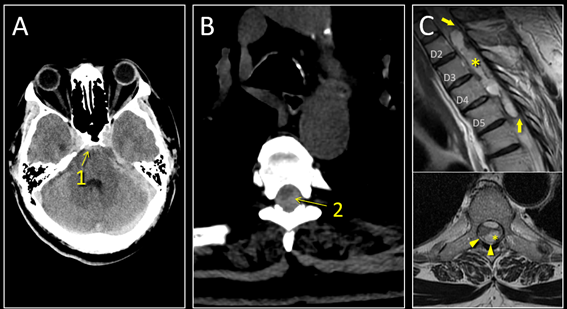

Caso del mes Noviembre 2025

Autor/Autores

Sara Septién Rivera; Josep Castell Aulet; Mildred Viveros Castaño. Área de Neurorradiología, Hospital Universitario de Bellvitge, Barcelona, España Mail: sseptien@bellvitgehospital.cat